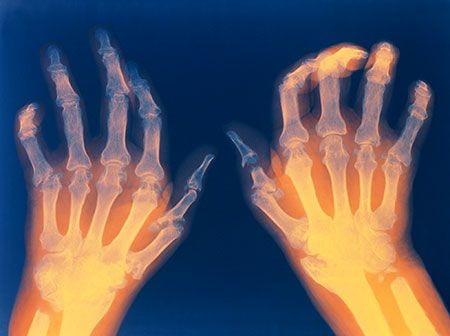

L’artrite reumatoide è una poliartrite infiammatoria cronica, anchilosante e progressiva a patogenesi autoimmunitaria e ad eziologia sconosciuta, principalmente a carico delle articolazioni sinoviali. Può provocare deformazione e dolore che possono portare fino alla perdita della funzionalità articolare.